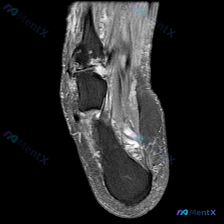

踝关节MRI提示软骨异常?这个病例的鉴别思路值得梳理

刚看到一份踝关节MRI病例,问题是询问影像上观察到的软骨异常相关发现,整理一下资料和分析思路分享给大家。

这是放射影像-踝关节MRI-T2序列-矢状位,系统评估整体结构如下:

- 骨与关节:胫距关节间隙正常,关节面轮廓可,距骨穹窿皮质连续,未见明确骨折线或弥漫骨髓水肿;距下关节、跟骨形态和信号均未见异常

- 跟腱:形态信号正常,连续性好,Kager脂肪垫信号均匀,无炎性渗出

- 重点异常:踝关节前方及深部软组织可见明显异常信号,胫距关节间隙内有中等量高信号液体聚集(关节积液),距骨颈部上方、胫距关节前方可见多发散在T2高信号,表现为弥漫性软组织水肿,累及前关节囊区域,不是局限于单一韧带

整体来看,骨骼结构完整,跟腱没有问题,核心异常就是中等量踝关节积液+前侧软组织弥漫水肿+软骨区域信号异常(软骨异常)。